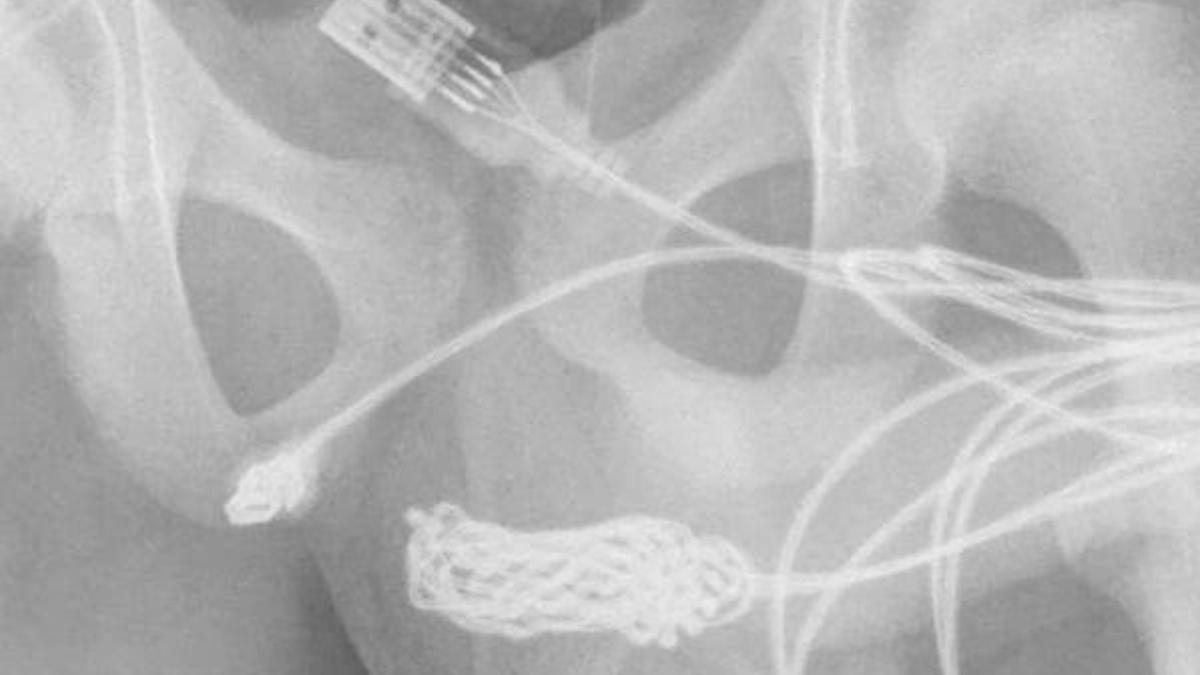

Çekilen röntgen filmi düğümün tam boyutunu ve pozisyonunu ortaya çıkardıktan sonra genç ameliyata gönderildi.

Cerrahlar penisi ve skrotumu çevreleyen kasları kestiler ve ardından düğümü kesip çıkardılar.

Sağlık görevlileri düğümü kesikten çıkarmayı başardı ve ardından kablonun geri kalanından ayırdı. Düğüm çıkarıldıktan sonra kablonun kalan iki parçası, penisten dışarı çekildi.